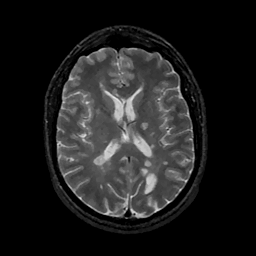

MR Study #11, May 5, 1991 -- Slice #29